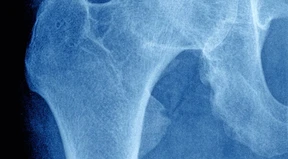

Deutsche Patienten bleiben nach der Hüft-OP einen Monat in der Klinik. In Amerika reicht ein Tag.